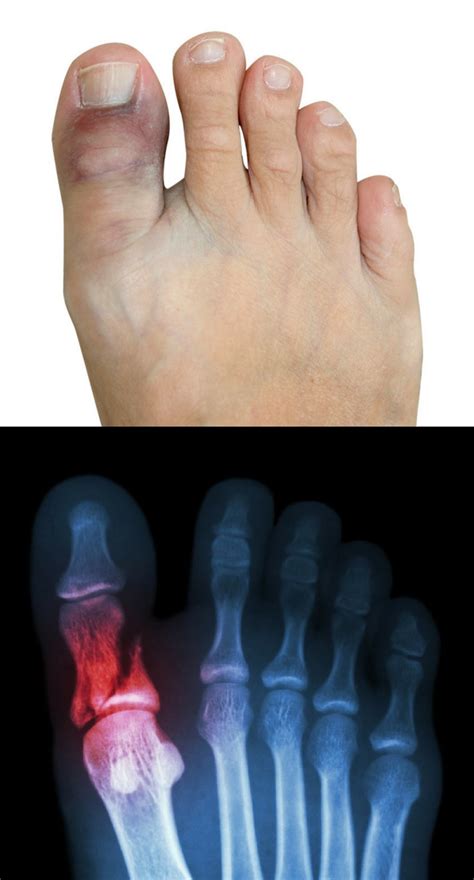

Dealing with a painful sprained big toe? Learn how to recognize common turf toe symptoms, effective home treatment strategies, and recovery timelines. Discover expert tips for pain relief, when to seek medical care, and essential rehabilitation exercises to help you regain mobility and safely return to your favorite physical activities. Start your path to recovery today.